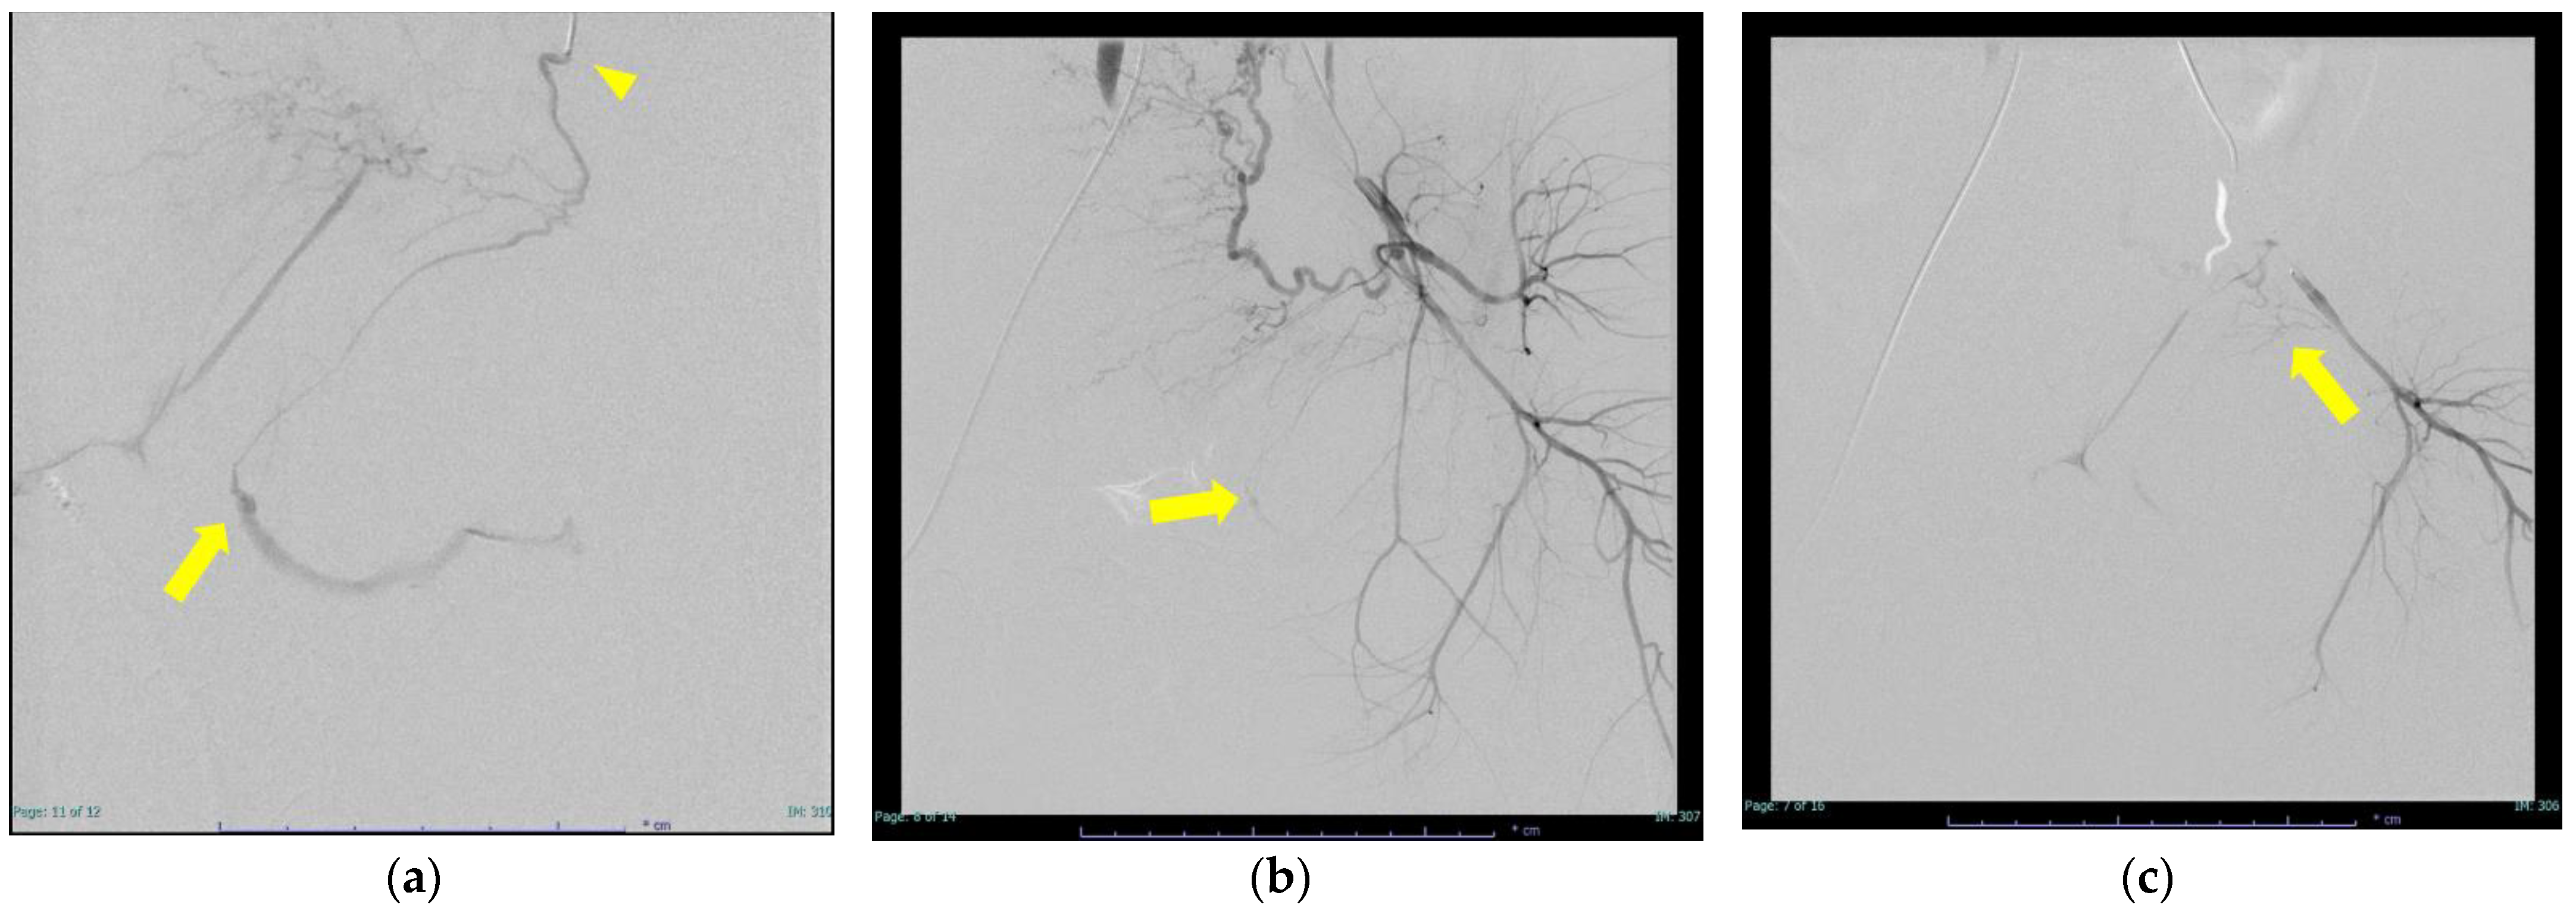

| 2 | 30 | 25 | 41/4 | primiparity | vacuum extraction | other | 3340 | 1385 | 1.07 | 26 | 0.96 | 505 | ― | ― | two vaginal branches of the lower left buttock artery (NBCA:lipiodol = 1:4 & NBCA:lipiodol = 1:3) 0.6 mL left uterine artery (gelatin sponge) | |

| 3 | 22 | 26.4 | 39/6 | primiparity | vacuum extraction | other | 3052 | 2050 | 0.91 | 21 | 1.02 | 271 | RBC12U, FFP8U | Hypertensive disorders of pregnancy | ― | uterine artery vaginal branch (NBCA:lipodol = 1:4) 0.2 mL bleeding from posterior collateral tract due to proximal obstruction 0.2 mL vaginal branch from the lower left buttock artery (NBCA:lipodol = 1:12) 0.3 mL |

| 4 | 30 | 23.2 | 40/4 | primiparity | normal vaginal delivery | other | 2986 | 1670 | 1 | 15.1 | 0.88 | 338 | RBC8U | ― | internal pudendal artery branch (direct branch from superior gluteal artery bifurcation level) (NBCA:lipodol = 1:3) 2 times 0.5 mL | |